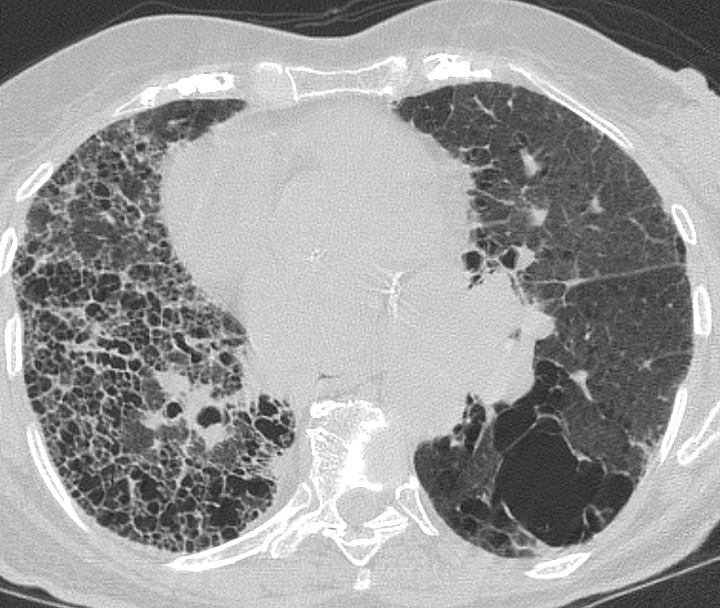

Gallery Pulmonary Fibrosis IPF Case 7c

Case 7c